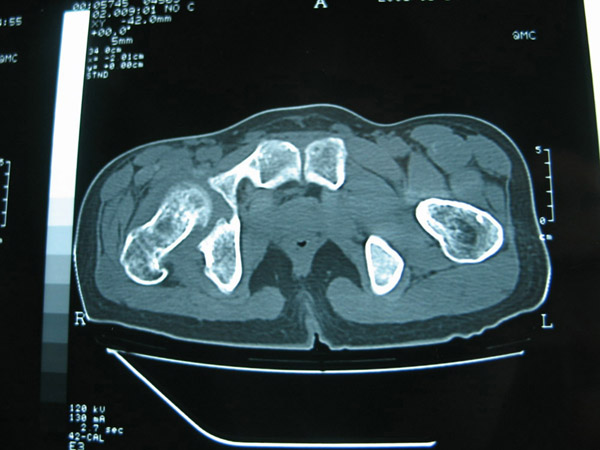

以下是引用卜一在2007-1-25 16:33:00的发言:[br]右侧髋关节股骨头及髋臼骨骨小梁疏松 粗糟,股骨头外形毛糟,软组织似肿胀,间隙略变窄.考虑:1 髋关节结核可能性大.2 缺血性坏死?3 化脓性髋关节炎?

以下是引用hhcckk在2007-1-25 17:18:00的发言:[br][br]支持髋关节结核,[br]依据关节面破坏,有脓肿,脓腔内有钙化,关节周围增生不明显,鉴别[br]1化脓性的病变增生明显,临床上有高热[br]2创伤引起的关节炎,无菌坏死不会引起关节面的破坏,而且不会在这么短的时间内出现[br]